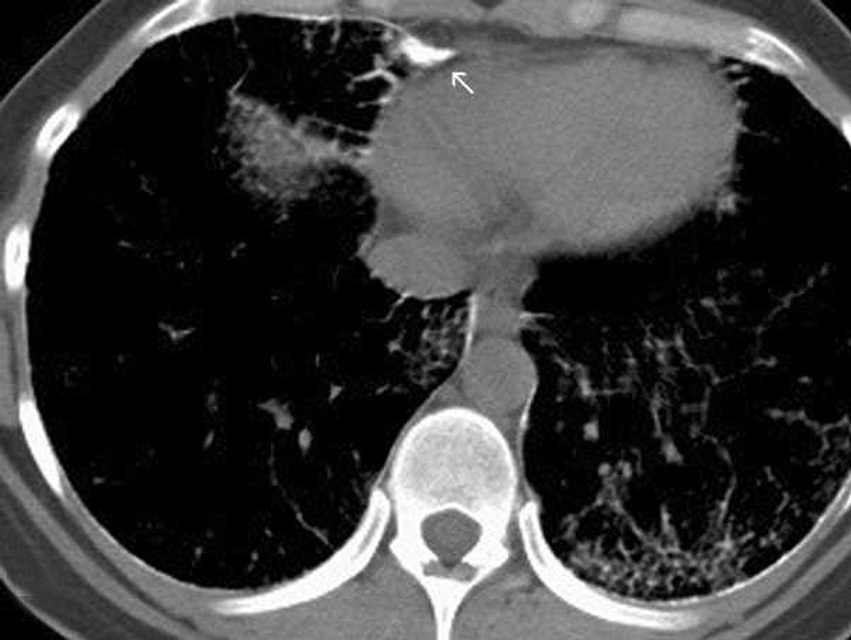

Las imágenes demostraron la presencia de puntiformes y difusas calcificaciones bilaterales, de predominio subpleural, en pleura mediastínica y en los septos interlobulillares. Los segmentos posteriores e inferiores estaban mayoritariamente afectos (fig. 2). También se visualizaron nódulos calcificados a nivel de segmentos anteriores (fig. 2B). El estudio detallado de alta resolución demostró un "patrón en empedrado" o crazzy-paving con marcado engrosamiento de los septos interlobulillares asociado a áreas parcheadas de aumento de la densidad en "vidrio deslustrado" o ground-glass, con mayor afectación de los segmentos posterobasales (figs. 3A y B). A nivel de los lóbulos superiores también se evidencian pequeños quistes subpleurales (fig. 3C).

Fig. 3. Las imágenes tomográficas de alta resolución demuestran la presencia de áreas mal definidas de aumento de densidad en vidrio deslustrado o ground-glass, con moderado engrosamiento de los septos interlobulillares, principalmente en los segmentos anteriores, adoptando en conjunto un "patrón en empedrado" o crazy-paving pattern (A). Secciones inferiores (B) demuestran la mayor afectación de las bases pulmonares. (C) También pueden visualizarse pequeños quistes subpleurales (flechas).